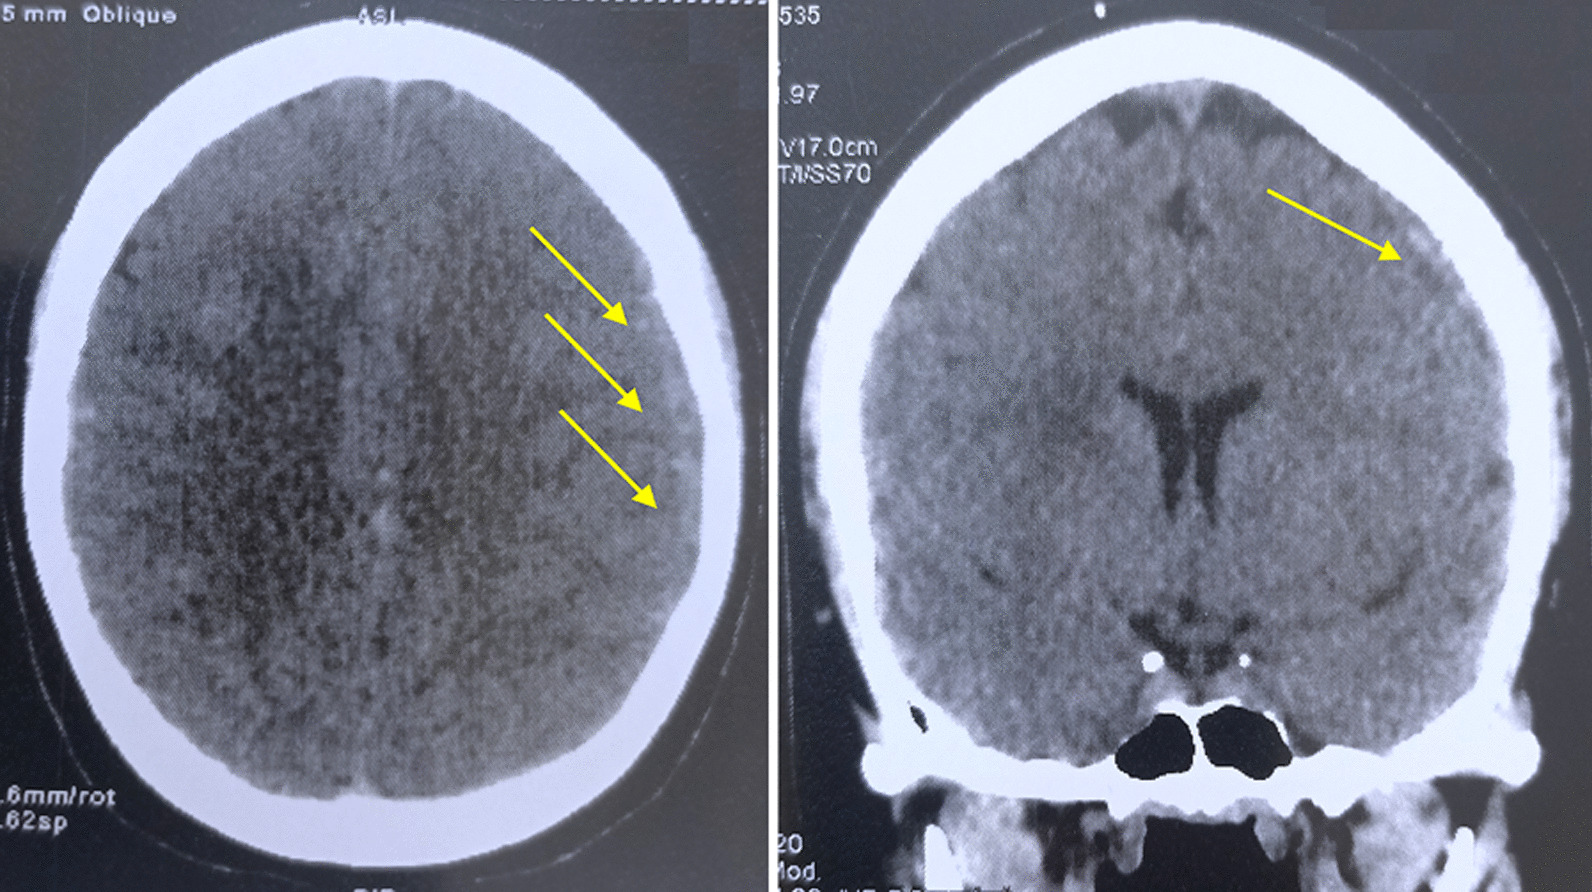

The evolution was favorable and the patient reported a total disappearance of headaches. A follow-up cerebral angioscanner performed at 1 month after treatment revealed a clear volume regression of the left fronto-parietal SDH (9 mm) compared to the previous examination and the persistence of a partial residual thrombosis of the superior longitudinal sinus achieving a partial repermeabilisation (Fig. 3).

Cerebral angioscan after 1 month of treatment, showing a 9 mm SDH blade (yellow arrows)

Cerebral angioscan at 3 months showed complete resolution of the chronic SDH and superior longitudinal sinus thrombosis with visible venous sinuses (Fig. 4). His clinical outcome at 3 months was excellent, justifying discontinuation of anticoagulant therapy and corticosteroids by degression.

Cerebral angioscan after 3 months of treatment, no parenchymal or vascular abnormalities